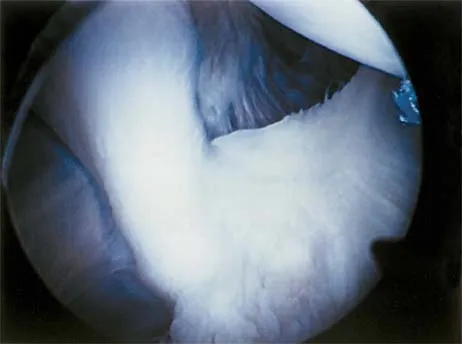

The view from an anterosuperior portal of the right shoulder shown in Figure 12 reveals which of the following findings?